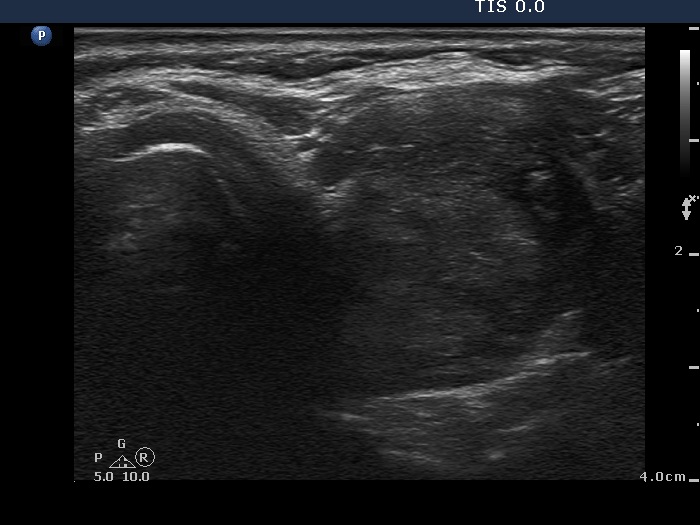

Follow-up investigation 11 months after the initial one (fourth row of images):

Ultrasonography. The degree of hypoechogenicity and vascularization increased compared with previous investigation.